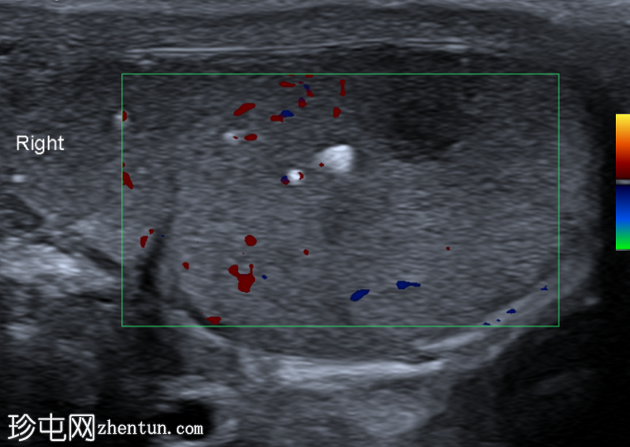

超声检查

右侧睾丸内可见一异质性肿块,大小约10 x 14 x 15 mm,包含实性和囊性成分。肿块内可见多发小钙化灶。彩色多普勒超声检查显示肿块内血流信号较少。